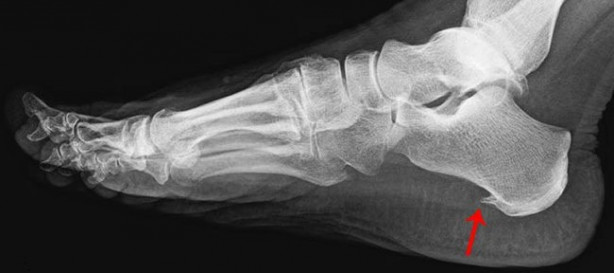

Topuk dikeni, aslında topuk kemiğinin alt kısmında diken benzeri çıntıya verilen bir isimdir.